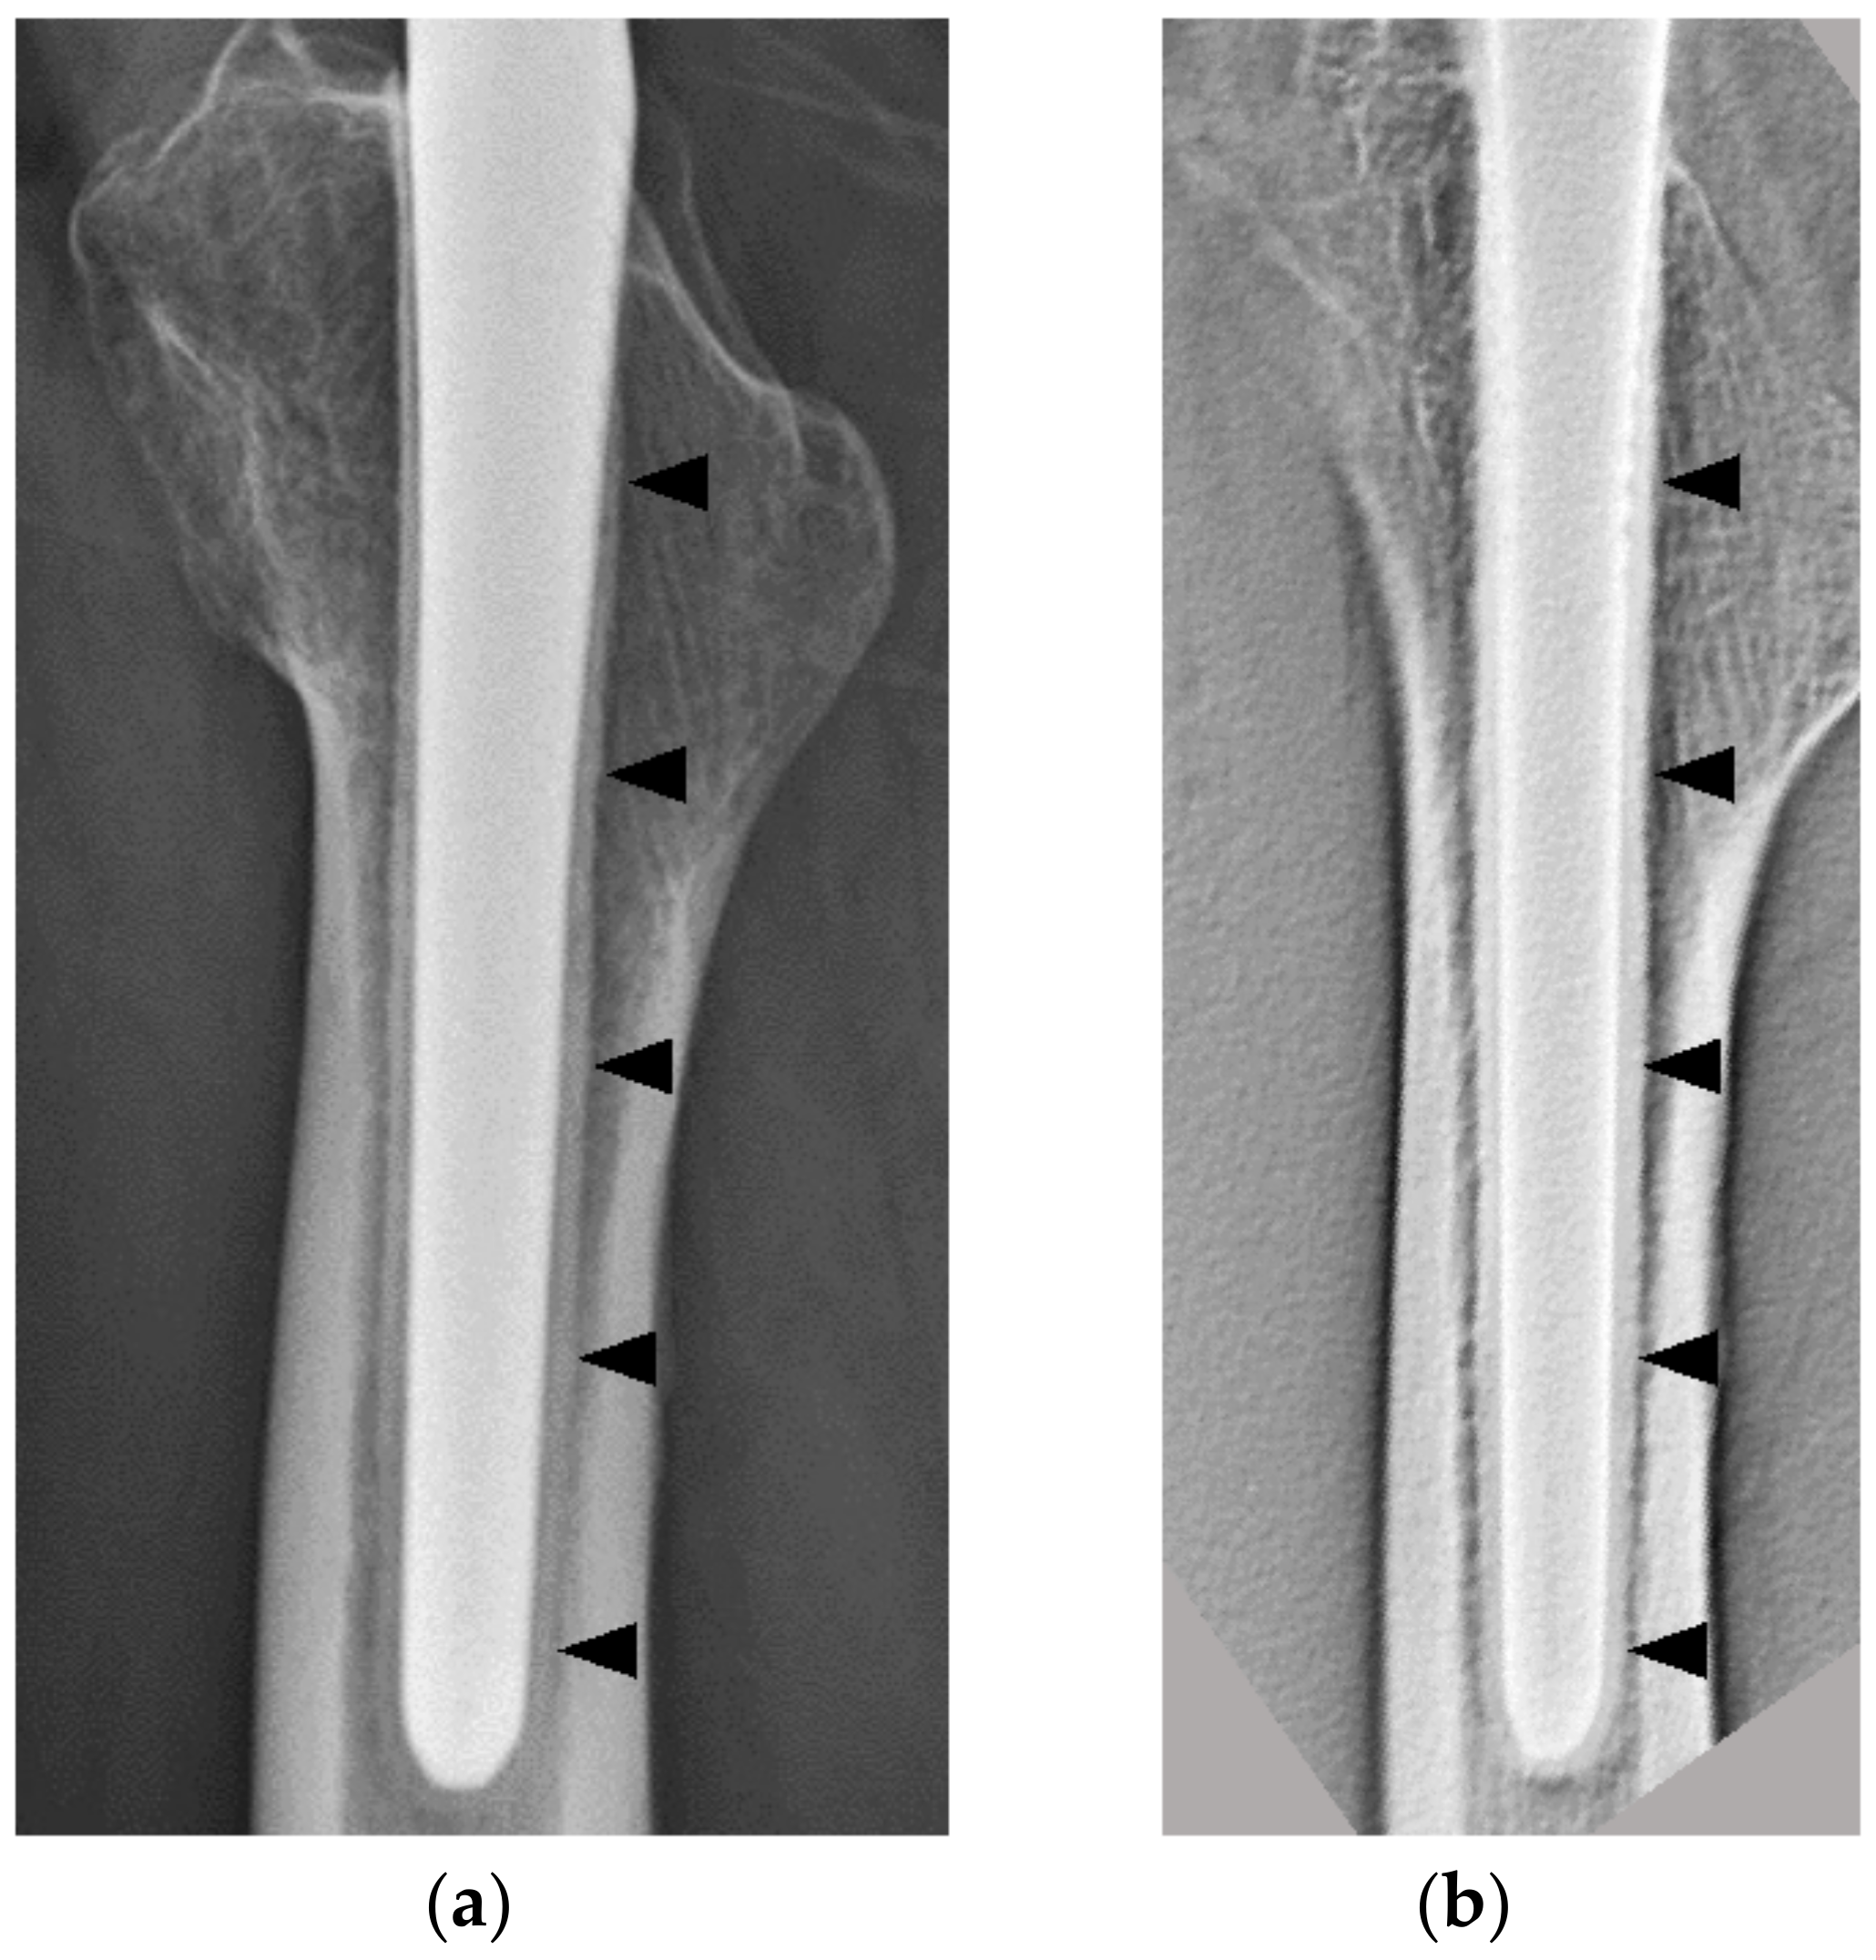

This time, DTS of a case with cancellous condensation revealed bone formation around the stem (Figure 2).

Figure 2.

An 83-year-old female patient 3 y after THA. (a) DTS (lateral view); there was bone formation surrounding the stem (black arrowheads). (b) Plain radiographs (lateral view) of the same patient as in (a); there was cancellous condensation similar to a reactive line (white arrowheads). THA, total hip arthroplasty; DTS, digital tomosynthesis.

In some cases, the SBF could not be seen on plain radiography, and in other cases, cancellous condensation was seen around the stem as a permeable line, which at first glance appeared as an RL (Figure 2). By contrast, on DTS, no radiolucent image was observed at the stem–bone interface in all cases, although the thickness of the SBF varied. Geesink et al., reported good results for HA-coated implants in biological fixation. Regarding the thickness of the HA coating, it has been reported that a thickness of 150 μm or more increases the risk of the coating peeling off due to fatigue fracture, while a thickness of 30–90 μm reduces the risk of fatigue fracture and allows the HA to function well. A thickness of 30–90 μm has been reported as a good thickness for the HA to work successfully while reducing the risk of fatigue failure [25]. Based on the above, the POLARSTEM adopted a 50 μm HA coating. Osseointegration is a process in which the lamellar bone adheres to the implant without fibrous tissue [26]. The micromotion of the stem is described as a fibrous tissue formation above 150 μm, mixed bone and fibrous tissue between 40 and 150 μm, and predominantly bone formation below 20 μm. Histological analysis has shown that the HA coating stabilizes the implant at an early stage and suppresses stem micromotion by promoting bone formation [26]. The results of the SBF observed in all patients in this study suggested that this is a stable stem response that does not result in micromotion. This may have a favorable impact on the long-term outcomes of the stem.